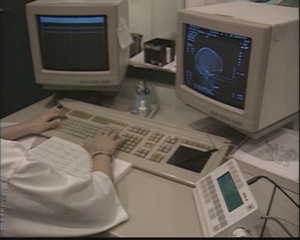

radiologia v18 |

|

|

|

| radiologia v181 |

radiologia |